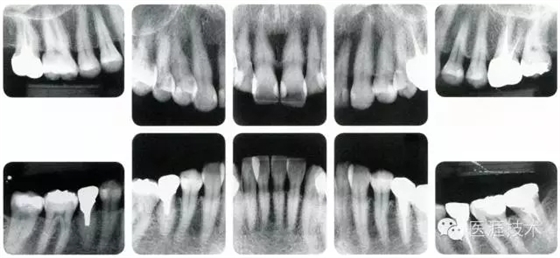

44歲牙周炎女性的臨床照片

640.webp (17).jpg

44歲患有糖尿病病史(未治愈)。菌斑控制不良。通過牙周探診,全頜有4~8mm的牙周袋,在X光片中可以看到上頜前牙處中度牙槽骨吸收,磨牙處重度牙槽骨吸收。二次齲齒和根面齲齒也有發(fā)生??梢钥吹礁∧[性腫脹,收到刺激后會(huì)出血。